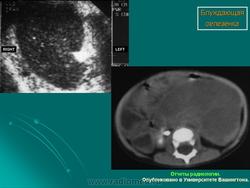

Селезёнки патология. Пнд, 09/09/2013 - 22:59 #1 Катенёв Валенти... Не на сайте Был на сайте: 7 лет 4 месяцев назад Зарегистрирован: 22.03.2008 - 22:15 Публикации: 54876 Спленомегалия Figure 46: Splenomegaly, contrast enhanced CT Пнд, 09/09/2013 - 23:00 #2 Катенёв Валенти... Не на сайте Был на сайте: 7 лет 4 месяцев назад Зарегистрирован: 22.03.2008 - 22:15 Публикации: 54876 Киста селезенки Figure 48: Spleen cyst, contrast enhanced CT Пнд, 23/09/2013 - 21:48 #3 Катенёв Валенти... Не на сайте Был на сайте: 7 лет 4 месяцев назад Зарегистрирован: 22.03.2008 - 22:15 Публикации: 54876 Полиспления ID: 18841 Polysplenia syndrome Dr Ian Bickle - 24 Jul 2012 Features of polysplenia syndrome (aka left sidedness or left isomerism) ... ID: 12761 Polysplenia syndrome , situs ambiguous, rectal mass Dr Amro Nazih Omar - 7 Jan 2011 Axial CECT demonstrates polysplenia, situs ambiguous, absent IVC an... Случаи и цифры Дело 1 Случай 2: Случай 3: Случай 4 Случай 5: situs inversus abdominalis